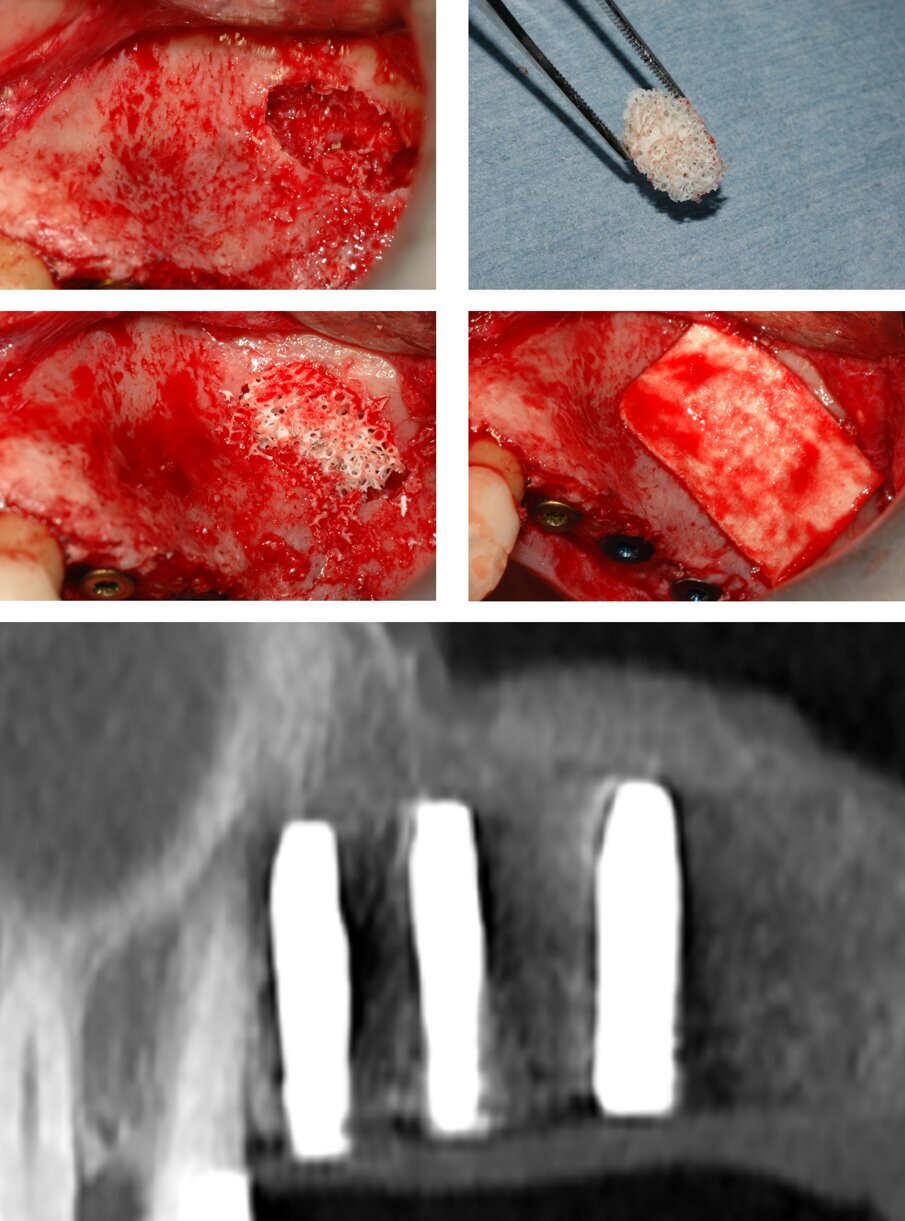

Prima dell’inserimento dei due impianti in posizione 2.6 e 2.7 si è proceduto a proteggere la membrana sinusale utilizzando un blocco osseo spongioso rigido, di origine equina, ottenuto attraverso un processo di eliminazione degli antigeni per via enzimatica (Osteoplant, Bioteck, Arcugnano); il blocco è stato tagliato con una pinza ossivora per ricavarne una porzione delle dimensioni adeguate al successivo inserimento al di sotto della membrana sinusale (Fig. 5); si è quindi proceduto ad inserire l’impianto in posizione 2.7 (Stone, IDI Evolution, Concorezzo), il cui apice, appoggiandosi al blocco appena inserito, non è entrato in contatto con la membrana sinusale (Fig. 5).

La cavità è stata quindi parzialmente riempita utilizzando un sostituto osseo di origine equina in granuli (Osteoxenon, Bioteck, Arcugnano), idratati con fisiologica sterile e miscelati con il particolato autologo prelevato precedentemente. Inserito il terzo impianto in posizione 2.6 (Stone, IDI Evolution, Concorezzo), il riempimento è stato completato utilizzando lo stesso sostituto osseo in granuli ed un’altra porzione del blocco impiegato in precedenza (Fig. 6). La finestra di accesso al seno è stata coperta con una membrana riassorbibile in collagene (Biocollagen, Bioteck, Arcugnano). Si è quindi proceduto alla sutura del lembo con una sutura non riassorbibile 5-0 (Monomyd, Butterfly, Cavenago). Non si sono osservate complicanze intra- o post-operatorie. La CBCT di controllo evidenziava il corretto posizionamento degli impianti, l’adeguato riempimento del seno, e la corretta interposizione del blocco osseo tra l’apice dell’impianto in posizione 2.7 e la membrana sinusale (Fig. 6). Dopo un adeguato tempo di guarigione, e seguite le usuali procedure di rimozione delle suture, scopertura degli impianti e condizionamento dei tessuti molli, a distanza di 4 mesi è stata consegnata la protesi definitiva in metallo-ceramica (Fig. 7). La paziente è stata controllata di seguito almeno annualmente. I controlli radiografici a un anno e a sette anni dall’intervento confermavano la conservazione dei livelli ossei perimplantari nel tempo, e la protesi appariva perfettamente funzionante (Fig. 7).

Fig. 5_Posizionamento di un blocco di osso spongioso di origine equina al di sotto della membrana sinusale: dopo avere ricavato un blocco di dimensioni adeguate, ed averlo idratato con soluzione fisiologica, lo stesso è posizionato all’interno della cavità. Si inseriscono il secondo e terzo impianto. L’apice dell’impianto in posizione 2.7 appoggia sul blocco osseo e non entra in contatto con la membrana sinusale.

Fig. 6_Il riempimento è completato con la miscela di osso autologo e sostituto osseo di origine equina in granuli; è utilizzato anche un altro frammento del blocco osseo precedentemente descritto. La CBCT di controllo evidenzia il riempimento corretto del seno ed il blocco osseo interposto tra apice implantare e membrana sinusale.